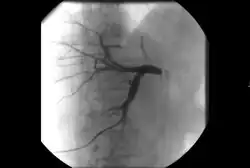

• Ангиография : визуализация кровеносных сосудов для выявления аномалий с использованием различных контрастных веществ, включая йодированный контраст, вещества на основе гадолиния газ CO2 .[3]